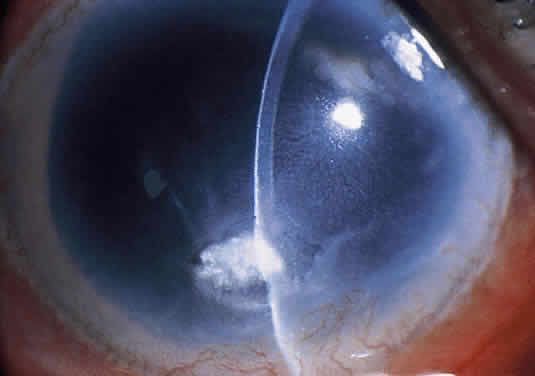

Corneal ulcers caused by S. pneumoniae are typically described as serpiginous or creeping and most often spread toward the center of the cornea. They are characterized by a gray-yellow disc-shaped ulcer with an overhanging margin at the advancing edge (Fig. 5). The ulcer usually progresses rapidly, extending into the deep stroma and often leading to corneal perforation. Extensive damage to corneal tissue, as well as a characteristic sterile hypopyon, are caused by the rapid production of bacterial exotoxin within the stroma.40,41

Fig. 5. Large, disk-shaped corneal ulcer caused by Streptococcus pneumoniae in an elderly woman. The presence of a sterile hypopyon is often associated with these ulcers.